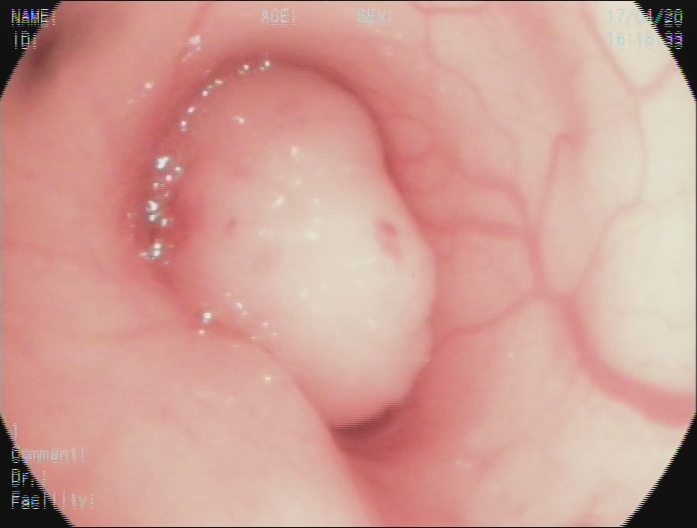

镜下圈套器切除、冷冻冻融治疗后

两年后支气管镜复查未见复查

两年前38岁的王女士健康体检,发现左主支气管7×10mm结节,遂到我院就诊,支气管镜检查见左主支气管内带蒂结节,表面光滑。经支气管镜使用圈套器完整切除结节,结节根部冷冻冻融治疗。病理提示为低度恶性的类癌。近日复诊,胸部CT、支气管镜检查均未见肿瘤复发。

肺结节通常在肺实质、肺外周,支气管内结节为其特殊类型,不仔细阅片的话容易漏诊。病变除了常见的支气管肺癌,还包括低度恶性或良性的肿瘤。良性肿瘤可考虑支气管镜下直接切除,恶性肿瘤还是首选外科切除。王女士的病灶在左主支气管下段,紧挨上下叶开口,外科手术创伤大,而带蒂病灶又基本完整切除。最终王女士选择了继续随访方案。幸运的是,经过两年观察,未见复发。不过后续还要定期复查,以防万一。